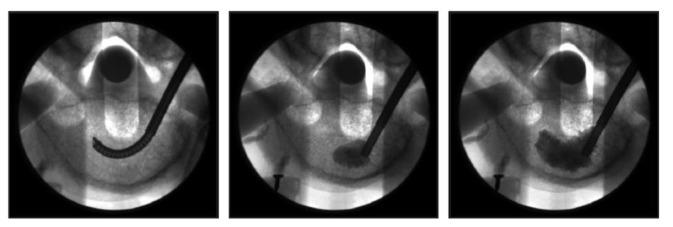

This ex vivo biomechanical pilot study utilized 16 osteoporotic cadaveric vertebral bodies in a standardized fracture model to compare unipedicular RF-TVA (n = 8) to bipedicular BK (n = 8). Four specimens from each group were tested in loaded and unloaded conditions. All specimens were imaged, assessed for height restoration, and sectioned to observe PMMA distribution. A subset of specimens underwent computed tomography scanning to assess cavity creation and trabecular architecture prior to cement delivery.

Anterior height restoration was greater with RF-TVA (median: 84%, interquartile range: 62%-95%) compared to BK (median: 69%, interquartile range: 60%-81%), although the difference did not achieve statistical significance (P = 0.16). Anterior height restoration was numerically greater under loaded (median: 70% versus 66%) and unloaded (median: 94% versus 77%) conditions with RF-TVA versus BK. RF-TVA produced more discrete cavities and less native trabecular destruction compared to marked trabecular destruction observed with BK. RF-TVA consistently showed a well-identified focal area of PMMA with an extensive peripheral zone of PMMA interdigitation, providing mechanical interlock into the adjacent intact trabecular matrix. In contrast, BK yielded little evidence of PMMA interdigitation beyond the boundaries created by the balloon tamp due to the crushed trabecular bone peripherally.

本体外生物力学初步研究使用 16 个骨质疏松性尸体椎体在标准化骨折模型中比较单通道 RF-TVA(n=8)与双通道 BK(n=8)。每组的 4 个标本分别在加载和未加载条件下进行测试。所有标本均进行成像、评估高度恢复,并进行切片观察 PMMA 分布。部分标本在输送水泥前进行计算机断层扫描以评估空腔形成和小梁结构。

RF-TVA 的前柱高度恢复更高(中位数:84%,四分位距:62%-95%),与 BK(中位数:69%,四分位距:60%-81%)相比,差异虽无统计学意义(P=0.16)。RF-TVA 在加载(中位数:70%对 66%)和未加载(中位数:94%对 77%)条件下的前柱高度恢复均大于 BK。与 BK 观察到的明显小梁破坏相比,RF-TVA 产生的空腔更离散,对原生小梁的破坏更少。RF-TVA 始终显示出 PMMA 的明确焦点区域,以及 PMMA 交织的广泛外围区域,为相邻完整小梁基质提供机械互锁。相比之下,由于周围小梁骨粉碎,BK 产生的 PMMA 交织痕迹很少超出球囊扩张所形成的边界。